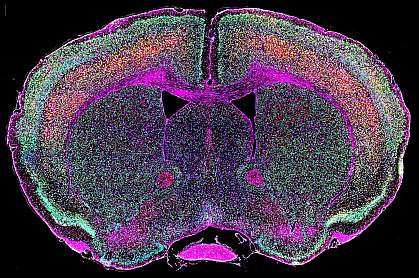

The scientists next examined genetically modified mice whose neurons expressed the HERV-K env gene. The mice died earlier than normal and had problems with balance and walking that progressively worsened with age. When the scientists inspected the animals’ brains, spinal cords, and muscles, they found that only motor neurons—the cells that control movements and die in ALS—were damaged. Cells in other parts of the nervous system remained healthy.